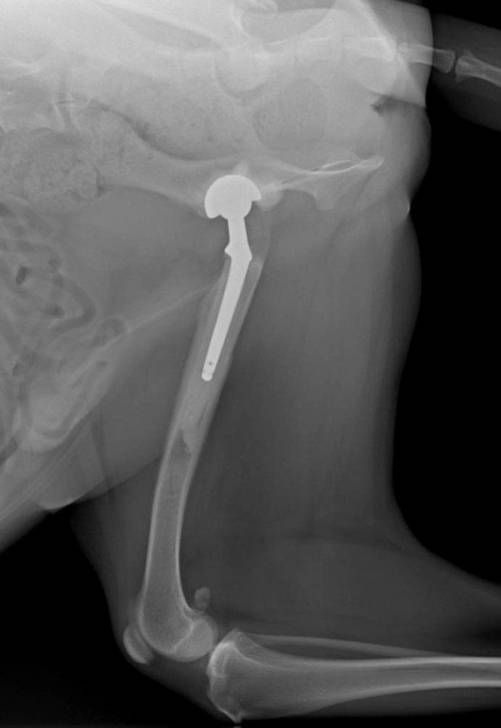

Une prothèse totale de hanche se compose d’une tête fémorale artificielle, en alliage titane ou chrome-cobalt, fixée dans le fémur, et d’une cotyle en polyéthylène. Elle recrée l’articulation atteinte.

Elle est posée chirurgicalement au cours d’une intervention durant en moyenne entre 75 et 90 minutes. Elle demande ensuite une lourde rééducation sur une période allant de 3 à 6 mois. A l’issue de cette dernière, le chien doit normalement avoir retrouvé toute sa motricité, et les douleurs avoir disparu.

On estime à plus de 95% le taux de réussite de la pose de prothèse de hanche pour chien. Les complications qui ont été constatées concernent des infections, des luxations de la hanche et des fractures du fémur ou de la cotyle.

La première prothèse de hanche pour chien fut posée en 1957. Depuis, plus de 40.000 chiens dans le monde ont bénéficié d’un tel dispositif. Les vétérinaires proposent cette solution lorsque les traitements (infiltrations, anti-inflammatoires...) ont échoué, après une destruction importante de la hanche suite à un traumatisme, ou encore dans le cas d’une maladie vasculaire résultant d’un cas de Legg-Calvé-Perthes.